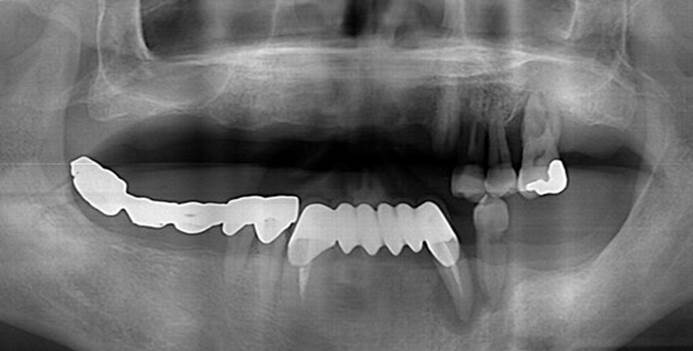

Clinical case: Full-mouth implants for mandibular & maxilla - restored using mixed prostheses

- Courtesy of Dr. Hyun Jun Kim, Korea -

“AnyRidge ensures long-term biological stability

& functionality even in

full-mouth rehabilitation case. ”